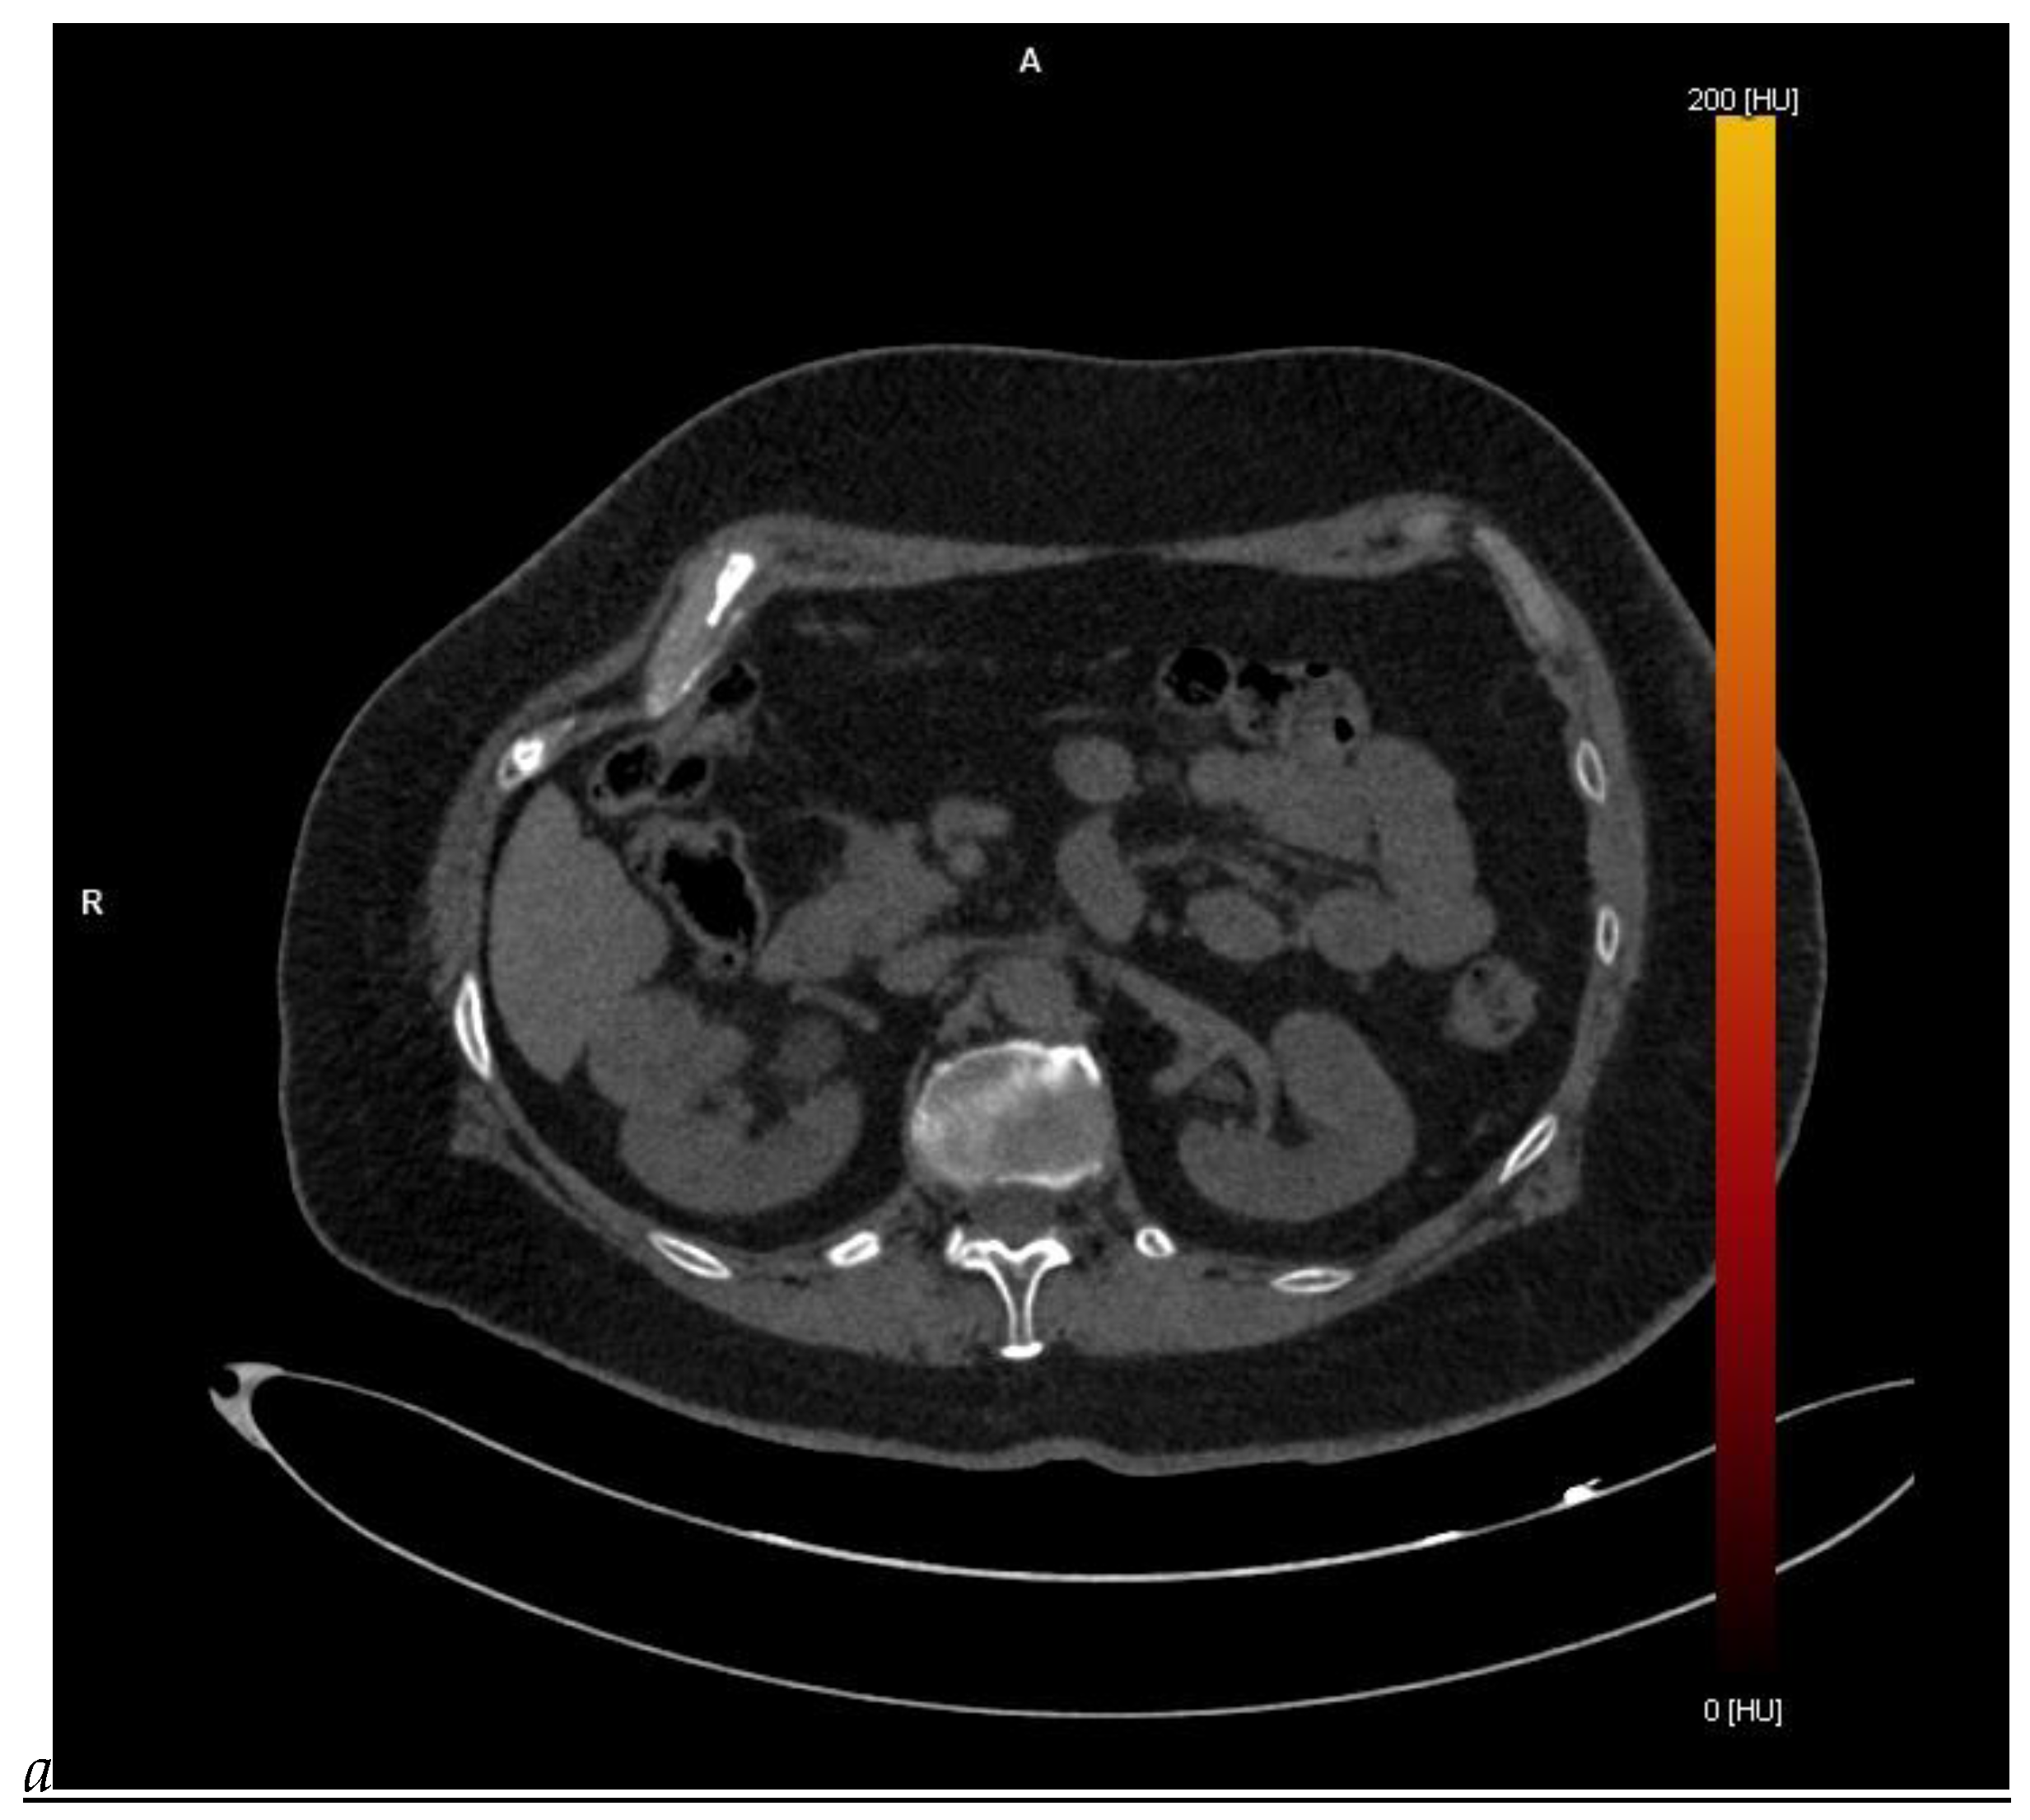

Figure 5.

Clear cell renal cell carcinoma in the right kidney of a 52-year-old-man. (A) Coronal T2-weighted fast SE image shows a large heterogeneous mass with areas of high signal intensity compared with renal parenchyma. Transverse in-phase (B,C) opposed-phase MR images show a subtle signal loss on the opposed-phase image. (D) The ADC map is heterogeneous with predominant areas of restriction of tumor diffusion. Transverse gadolinium-enhanced T1-weighted gradient-echo spoiled MR images in (E) corticomedullary, (F) nephrographic, (G) and delayed phase images show intense and rapid peripheral enhancement during the arterial and nephrographic phases followed by a rapid washout of contrast on the delayed phase. Central necrotic areas do not enhance. (H) Macroscopic view of the lesion after radical nephrectomy. The lesion appears heterogeneous. Courtesy of Pr S. Ferlicot, Department of Pathology, Bicêtre Hospital.